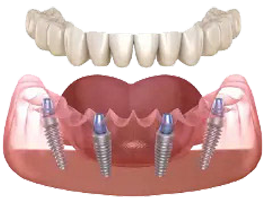

Dantura Fixă pe Implanturi este o opțiune de tratament pentru situațiile în care mai mulți dinți lipsesc sau nu mai pot fi salvați. Procedura presupune folosirea unui număr de implanturi, poziționate pentru a susține o lucrare fixă.

Această abordare permite restaurarea funcției de masticație și îmbunătățirea confortului zilnic, oferind o alternativă la protezele mobile. Planificarea se face digital, iar fiecare etapă este adaptată situației dvs. clinice.

Tratamentul poate include implanturi All-on-4/6 sau implanturi zigomatice, în funcție de volumul osos disponibil. Soluția este potrivită pacienților care își doresc o lucrare fixă și stabilă, atunci când pierderea dentară este mare.

Dantura fixă pe implanturi este o soluție modernă, stabilă și estetică, ce înlocuiește complet dinții lipsă cu o lucrare fixă ancorată pe implanturi, oferind senzația și funcționalitatea unor dinți naturali.